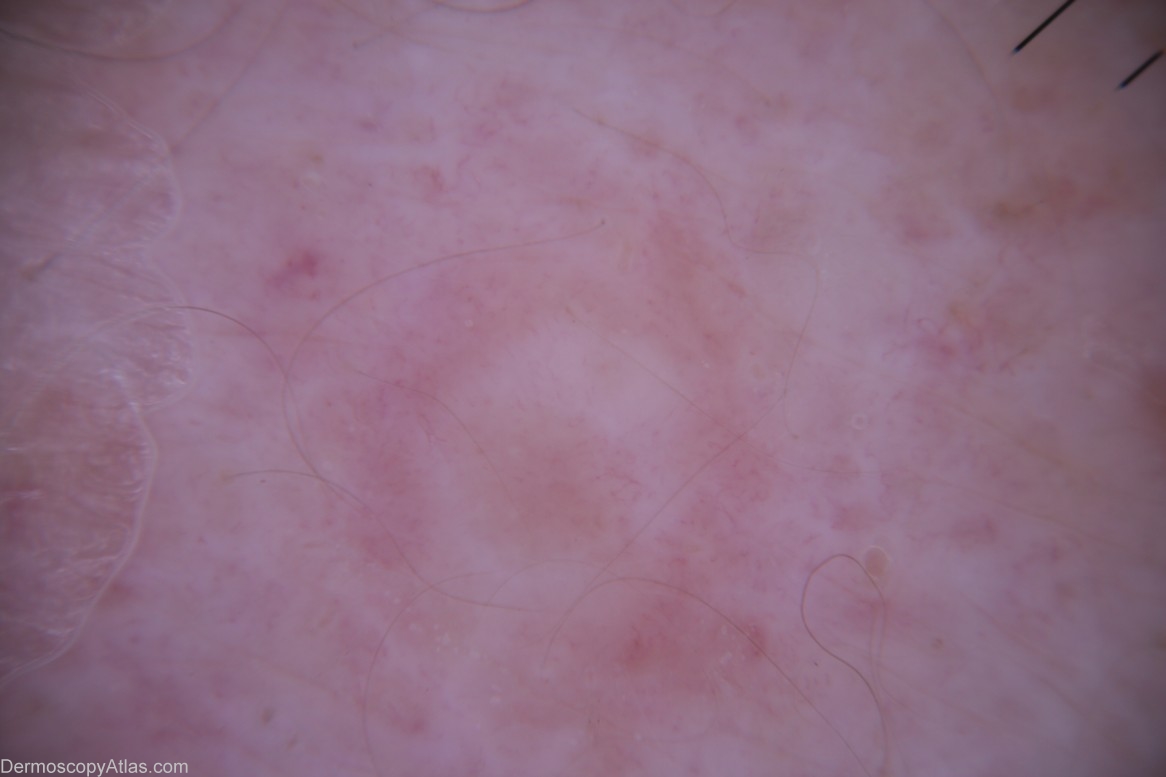

Diagnosis: Melanoma amelanotic

History: This 87 year old veteran of World War 2 had a regular skin examination ( Past history of non-melanoma skin cancers) and this small papule could not be confidently diagnosed clinically. It was thought to be benign but NMSC needed exclusion. It came back after a 4mm punch biopsy removal of the visible lesion as a level 3 amelanotic melanoma (Breslow thickness 1.3mm) with complete regression of the epidermal component. A further 1.5 cm clearance was obtained and the report came back as superficial spreading amelanotic melanoma (small residual level 2 0.3 mm thick)cleared by only 5mm. In retrospect, especially with enhancement of the image by Dr. Lester Cowell, the large insitu amelanotic melanoma can be visualised.